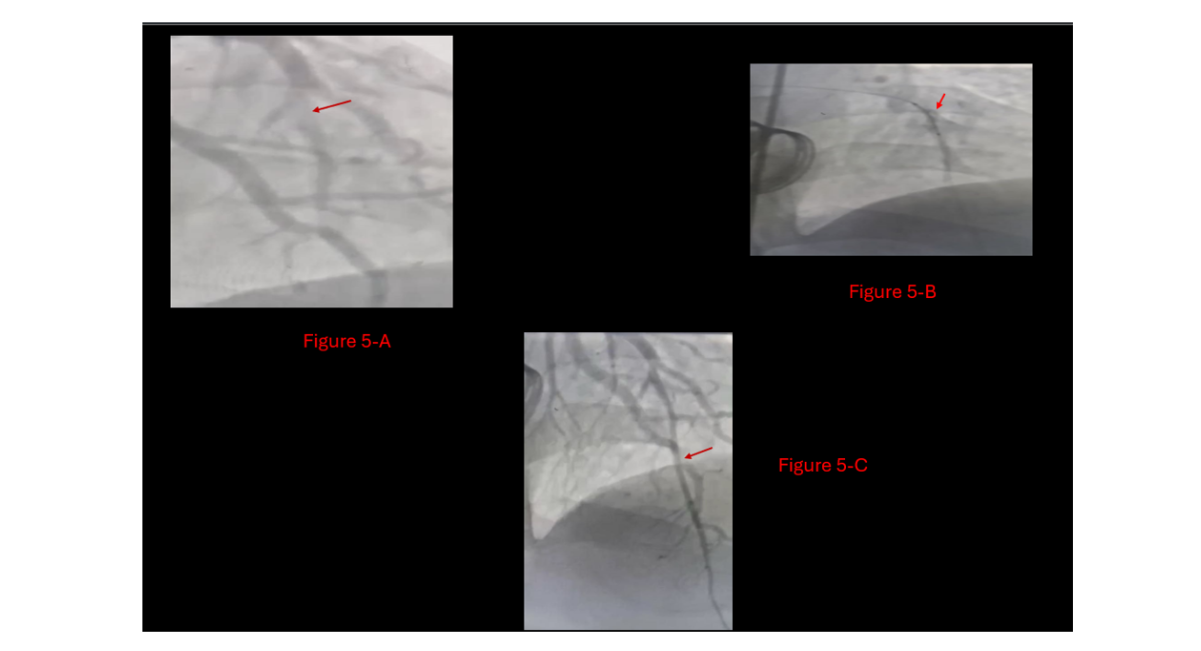

The patient was admitted and started on therapeutic intravenous enoxaparin (Clexane®). On hospital day 3, a second-look coronary angiography showed partial thrombotic obstruction of the LAD, which was successfully treated with two further aspiration runs (Figure 5). Additionally, the aortic valve was now fully mobile with no evidence of residual thrombus (Video 2, Video 3). The patient was discharged on day 4 with a therapeutic INR, well-functioning aortic and mitral valves on echocardiogram, without any stent placement. His home medications included warfarin 5 mg daily and clopidogrel 75 mg daily.

Figure 5: Last Catheter visit,

A: LAD showed residual thrombus at Diagonal 1,

B: second look with Balloon dilation at different levels of LAD,

C: Final result, patent LAD with TIMI flow III, without stenting need